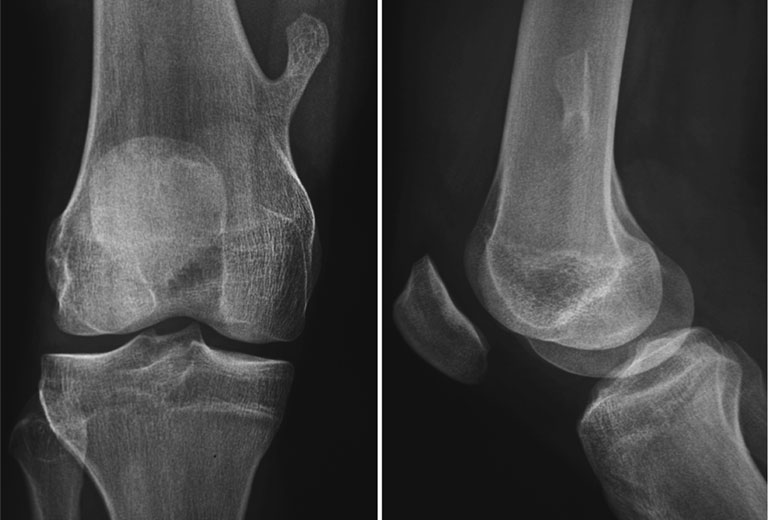

Có nhiều phương pháp hình ảnh hỗ trợ trong việc chẩn đoán u nang xương đơn độc. X-quang là phương pháp chính được sử dụng để chẩn đoán u nang xương đơn độc. Trên hình ảnh X-quang, u nang xương có những đặc điểm như sau:

CT-Scan được sử dụng để đánh giá nguy cơ gãy xương và đánh giá bề dày của thành nang. Trên hình ảnh CT-Scan, có những dấu hiệu như sau: